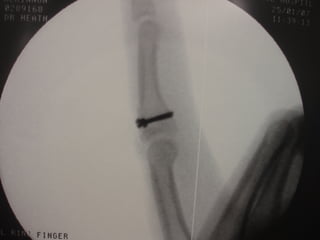

Dorsal PIPJ Dislocations

ď‚§ Operative Mx:

ď‚§   Debridement & joint washout for open injuries

ď‚§   Dorsal block splinting

ď‚§   ? Role of primary VP repair

ď‚§   Other specific techniques for unstable PIPJ injuries:

ď‚§   Dynamic skeletal traction

ď‚§   Extension block pinning

ď‚§   Trans-articular pinning

ď‚§   ORIF

ď‚§   Volar plate arthroplasty

ď‚§   FDS tenodesis (for chronic hyperextension deformity of PIPJ)

ď‚§ Complications of operative Mx:

ď‚§   Redisplacement

ď‚§   Angulation

ď‚§   Flexion contracture

ď‚§   DIPJ stiffness